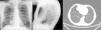

Varón de 65 años de edad, exfumador, estudiado en la consulta de neumología en 2009 por una imagen de aumento de densidad en el ángulo cardiofrénico derecho. En la TC torácica se apreció una masa sólida de 29×34mm, de bordes lisos y bien delimitados, en el ángulo cardiofrénico derecho, sugerente de quiste pleuropericárdico. El paciente no acudió a consulta hasta septiembre de 2015, fecha en la que se observó en la radiografía de tórax de control un aumento de tamaño de la lesión descrita (fig. 1). En la TC torácica se evidenció una masa sólida en el ángulo cardiofrénico derecho, con un diámetro mayor de 6cm, que se puso en relación con un probable tumor fibroso pleural (fig. 1). Posteriormente se realizó resección quirúrgica de dicha lesión. El estudio anatomopatológico fue compatible con un timoma de tipo AB de la clasificación de la OMS, seudoencapsulado, que respetaba los márgenes quirúrgicos de resección.